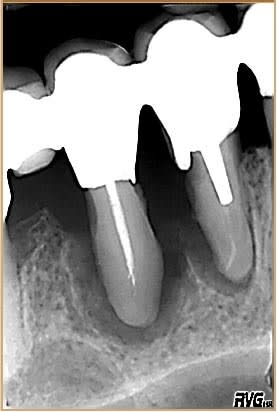

Qu'est-ce qui s'est passé d'après vous ? Les deux prémolaires supportent toutes seules la latéralité ? Est-ce que les deux endos pourries sont suffisantes pour expliquer cette horreur ? Ta patiente n'aurait-elle pas des problèmes de santé ?

Perso je ne suis pas sur du tout vu l'alvéolyse qu'il y ait au départ un pb endo mais je peux me tromper

Si tu cherches à récupérer ces dents, tu n'y arriveras pas au long terme.

Ce genre de racine en baguette de tambour, le type de lésion parodontale malgré la contention appaemment correcte, les prothèses fixes étant bien dessinées, ...???